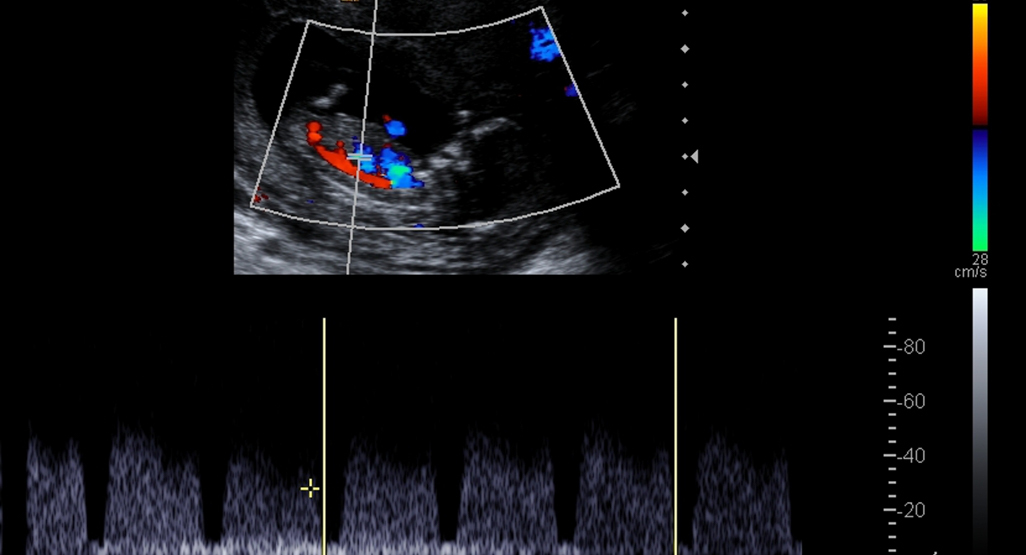

Color Doppler

Vascular Medicine: Color Doppler assesses blood flow in arteries and veins, detecting conditions like deep vein thrombosis (DVT) and peripheral artery disease (PAD).

Obstetrics: In prenatal care, it monitors blood flow in the umbilical cord and fetal vessels, ensuring the health of the developing baby.